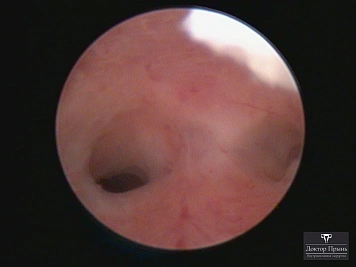

Как правило, синехии находят при УЗИ. Когда по УЗИ патологии нет, а симптомы есть, выполняют гистероскопию – это золотой стандарт в определении синехий.

Гистероскопия позволяет не только увидеть спайки, но и сразу вылечить, т.е. рассечь их. Большинству пациенток подойдёт офисная гистероскопия без наркоза и госпитализации. Среднее время операции 15 минут. Иногда требуется 2-4 операции, чтобы восстановить полость матки.

Синехии, рассечённые Прынь Д.В.